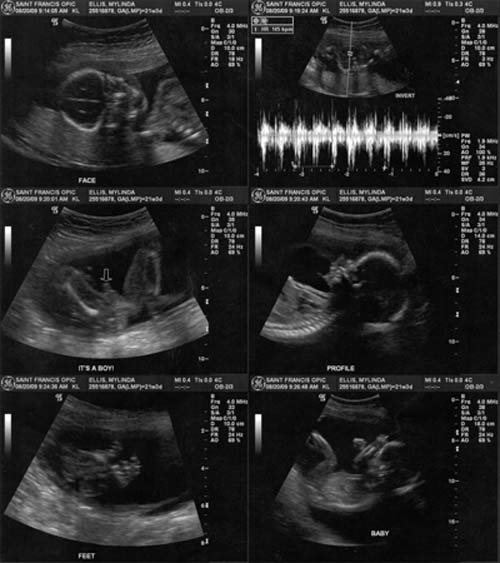

This was a type 2 ultra sound it is older but my printer would not scan. Kodak was nice enough to send me another one with the same problem. However after getting two new  printers and finally upgrading (at the expense) to a different model we have a working printer.

I went to the Dr.'s yesterday and these are the latest photos. I am not a real big fan of the 3D ultra sounds as the baby look alienish but thought I would share them anyway.

How great it is to live in a time where we have all the modern technology to be able to see photos of the unborn babies. He is doing well and weights 4 1⁄2 lbs. He is very active and I'm sure will give me a run for my money. Still don't have a name but I think we will decide when we see him. Hope everyone is doing well. Love ya, Zeke, Mylinda, Lauren and the boy.